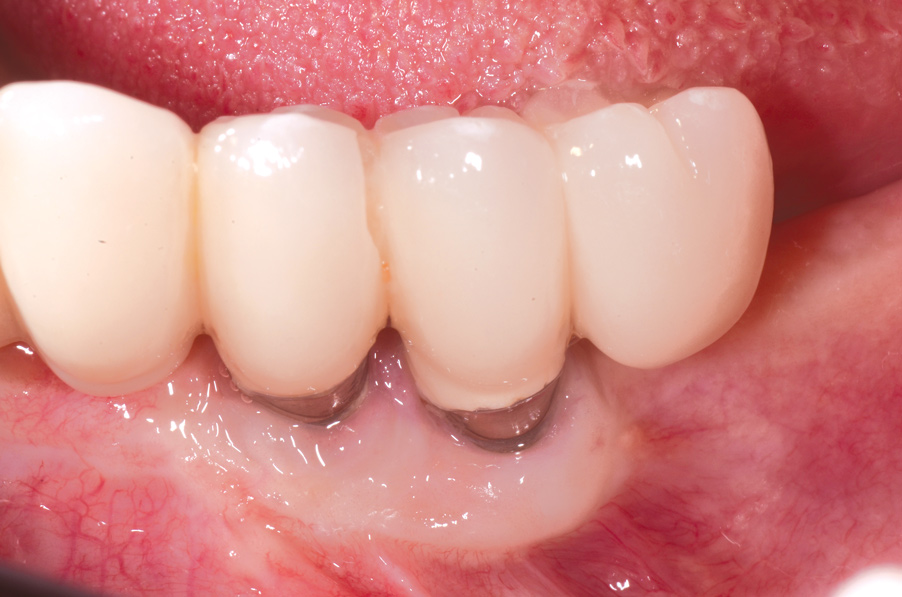

Dental implants have revolutionized the way in which clinicians treat and restore partially and fully edentulous patients and have demonstrated success for managing a broad range of clinical dilemmas. While implants have been highly predictable and have achieved long-term success, they are not immune from complications associated with improper treatment planning, poor surgical and prosthetic execution, material failure, and inadequate or infrequent maintenance. Among these problems are the biologic complications of peri-implant mucositis and peri-implantitis, which are inflammatory conditions in the soft and/or hard tissues surrounding dental implants (Figure 1 through Figure 4).1,2

Fig 4. Clinical view of the area 3 months post-therapy. Shallow probings of 3 mm were present around the dental implants with absence of bleeding. However, the mucogingival deformities remained on the premolar implants and would require treatment.

Figure 4